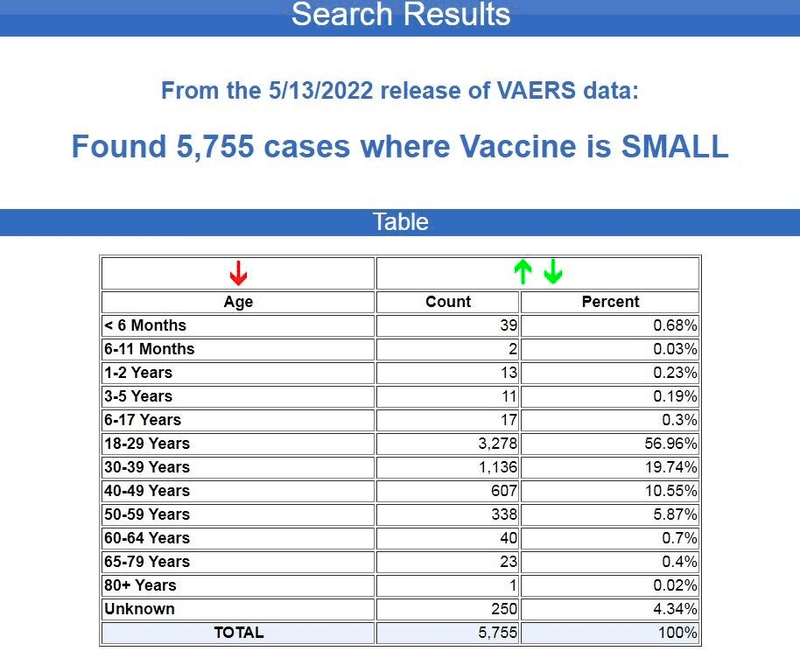

VAERSで報告された天然痘ワクチン後の傷病死亡から、年齢別内訳を紹介します。

ご覧のとおり、約77%が18歳から39歳までの若年層で報告されています。